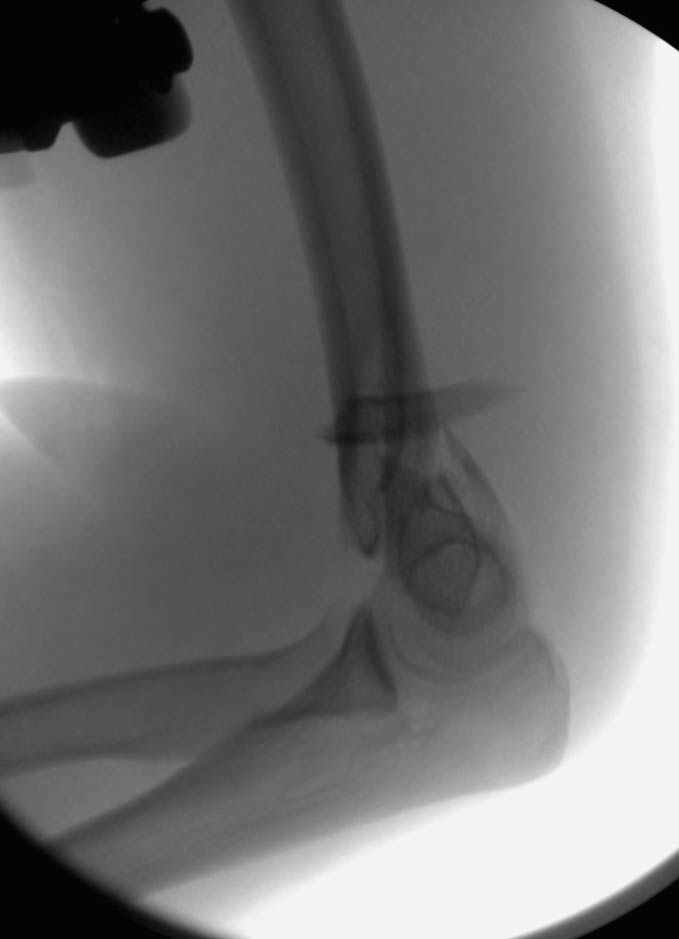

На шестой день сделали открытую репозицию чрезлоктевым доступом двумя locking plate, локтевой нерв был ушибленным, после операции положительная динамика в Flexor Carpi Ulnaris. Фиксацию локтевого отростка произвели tension band technique с дополнительным шурупом.

Этапы операции на снимках....